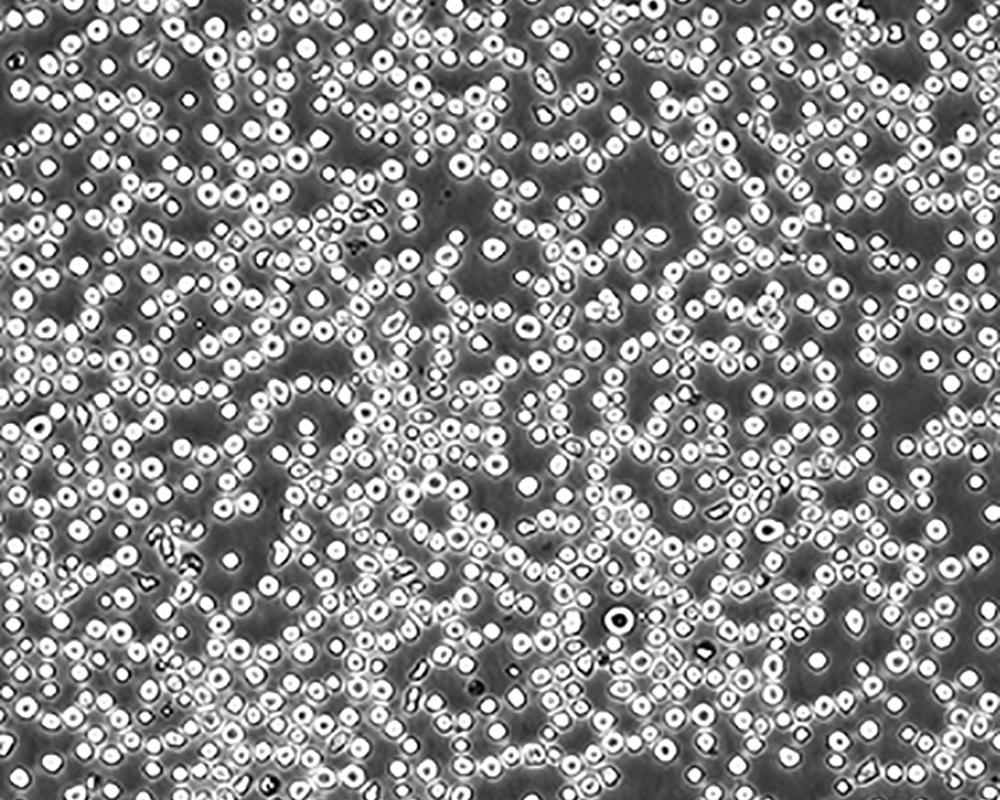

生長特性 suspension

形態特征 lymphoblast

傳代方法 1:2-1:4

細胞描述 CEM/C1是人T細胞白血病細胞株CCRF-CEM(見ATCC CCL-119)具有喜樹堿抗性的衍生株。1991年細胞株選擇并亞克隆了對CPT的抗性。細胞表現出對CPT類似物水溶性的托泊替康和非水溶性的9-氨基-CPT及10,11-亞甲二氧基-CPT具有交叉抗性。CEM/C1細胞對CPT的敏感性較母系CEM細胞低31倍。CEM/C1細胞表現非典型的多藥抗性和轉換拓補異構酶I催化活性。對CPT的抗性維持6個月以上。